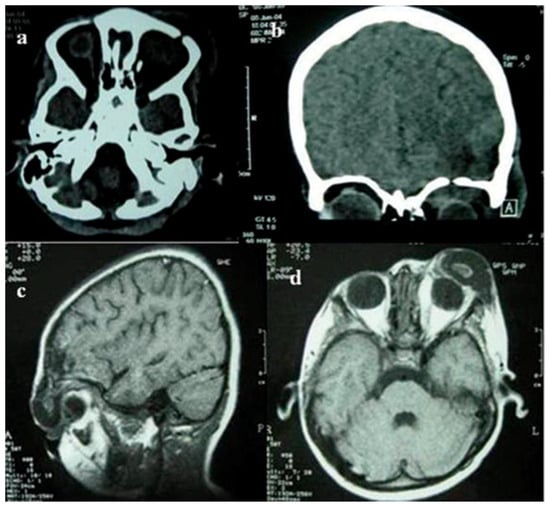

:Case Report